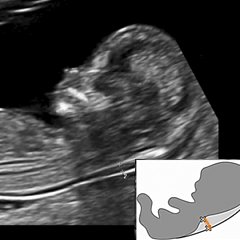

Позднее, во втором и в третьем триместре, есть возможность подробно, детально различить и изучить сердечные клапаны и камеры. Изменение числа сердечных сокращений во втором и третьем триместре может говорить о страдании плода, нехватке кислорода и питательных веществ.

Уже начиная с первого исследования можно определить сердцебиения плода (в норме ЧСС составляет 120-160 ударов в минуту). Отклонение показателей ЧСС при первом исследовании - увеличение или уменьшение числа сердечных сокращений - может служить признаком того, что у недавно зародившегося плода имеется порок сердца.